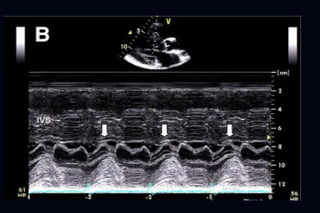

Hallazgos ecocardiográficos  La variante más común (hipertrofia septal asimétrica)  Hipertrofia del septum en toda su longitud a costa de la cavidad  Razón de pared septal/posterior > 1,3  Curvatura reversa del septum  Hipertrofia de predominio “superior” es más frecuente en HTA y con envejecimiento

• 41.

• #42 Figure 1 Characteristic Echocardiographic Features of Obstructive HCM (A) Parasternal long-axis view depicting severe asymmetric septal hypertrophy and systolic anterior mitral valve motion (arrowhead) ; (B) M-mode across the mitral leaflet...

• #43 Figure 1 Characteristic Echocardiographic Features of Obstructive HCM (A) Parasternal long-axis view depicting severe asymmetric septal hypertrophy and systolic anterior mitral valve motion (arrowhead) ; (B) M-mode across the mitral leaflet...